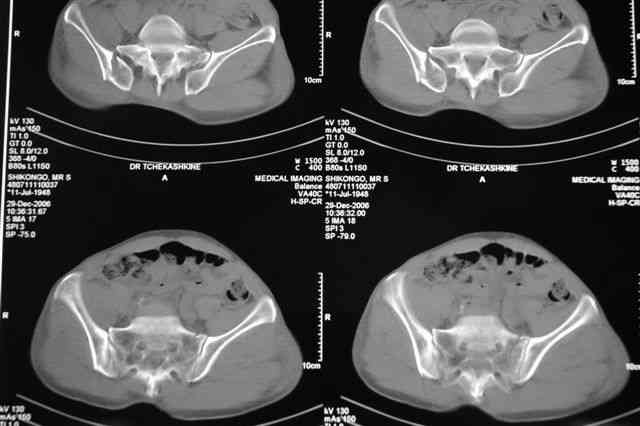

В приложении отправляю послеопер. снимки бедра и лодыжки обсуждаемого вчера больного.

В приложении послеоперационные картинки.